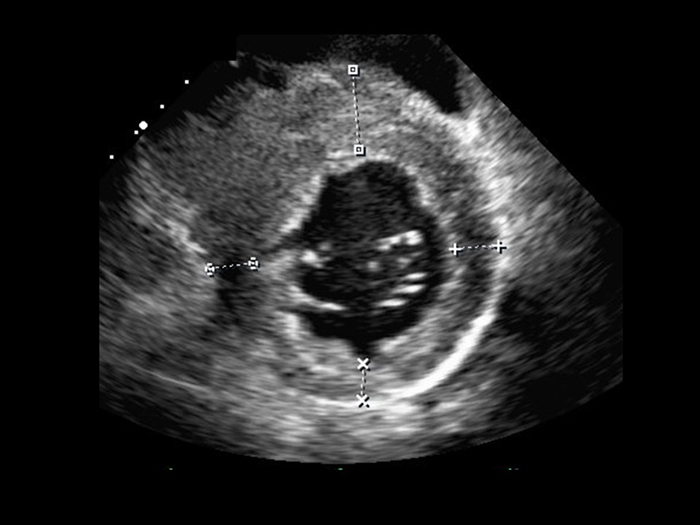

心エコー

現在心臓の画像検査では

基本的な検査の一つです。

↑写真のように

横になって機械を当てるだけの

簡単な検査ですが、

心臓の動き・形・弁膜症の有無や

その他の心臓の病気を

見つけるための重要な検査です。

心エコーの費用

9000円かかりますが、保険の1割〜3割負担で

900円〜2700円前後になります。